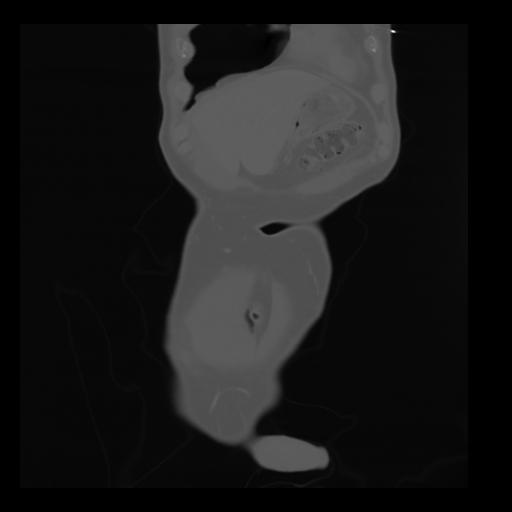

35 CUERPO,CE,Coronal,3.000,CUERPO,Coronal,